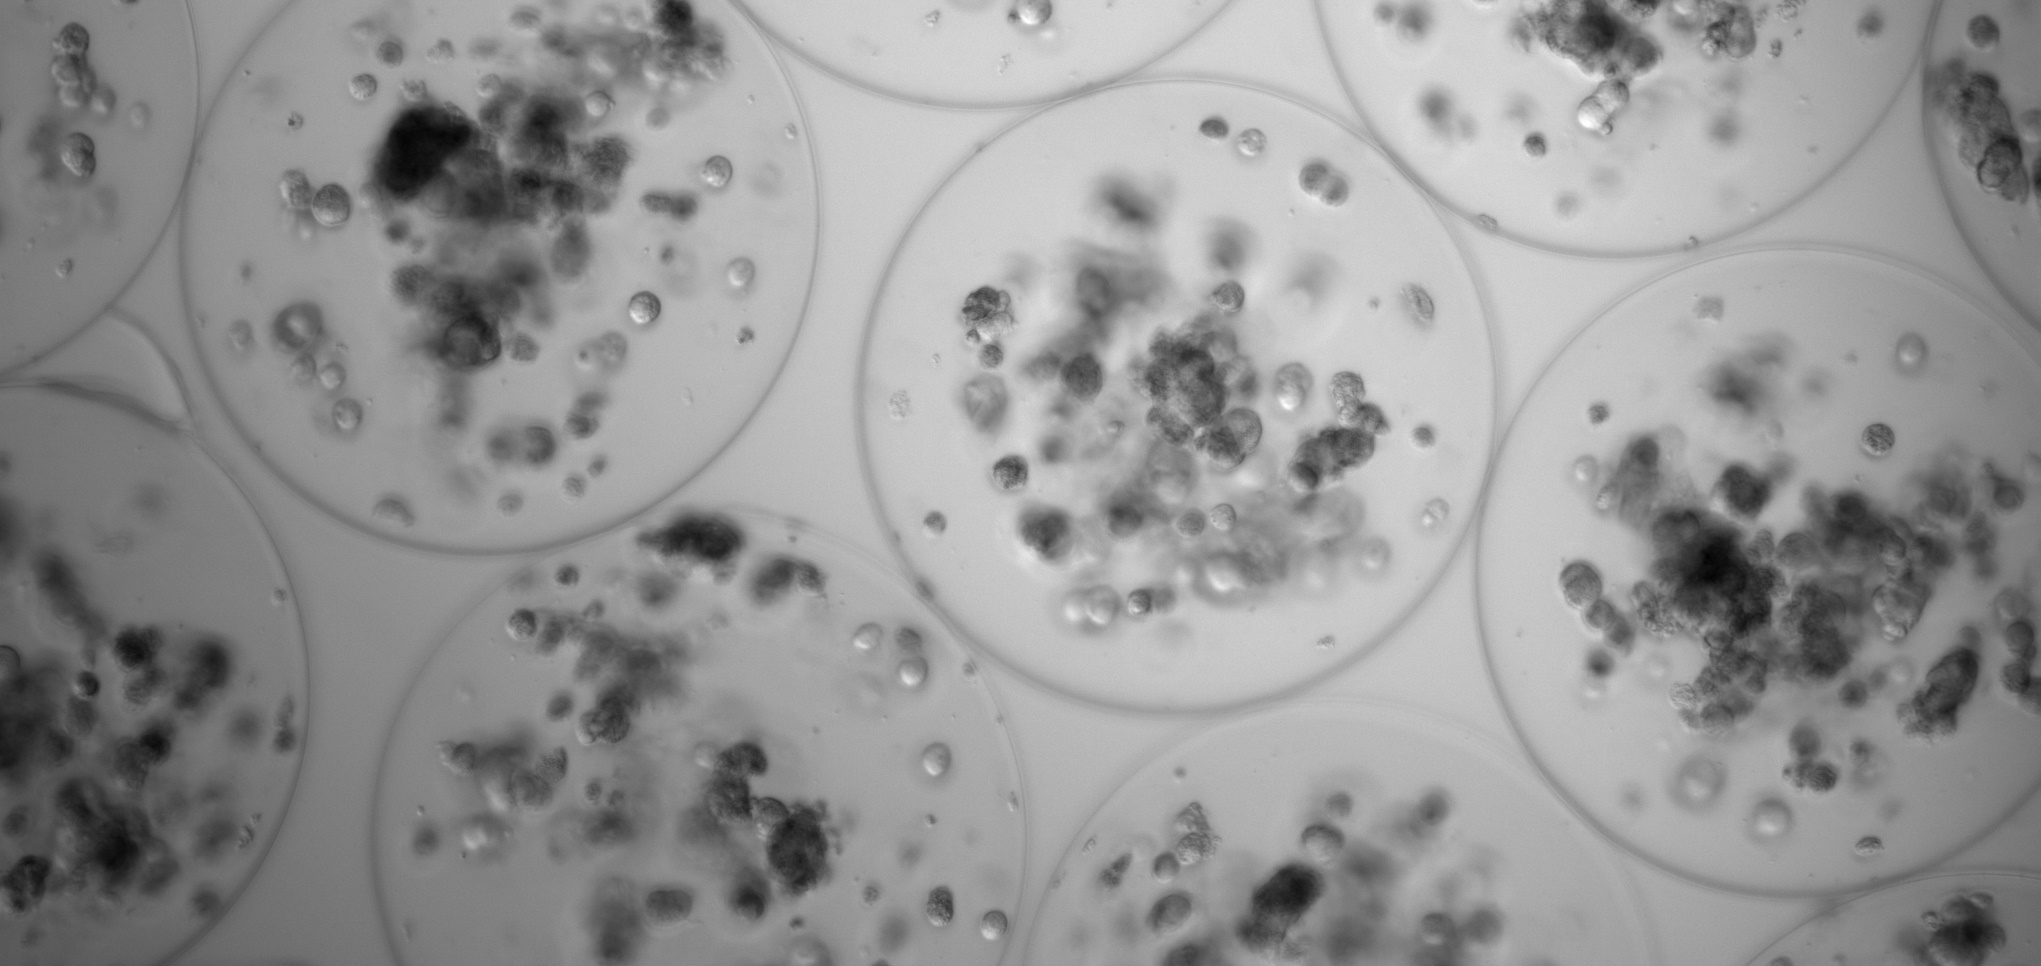

The above mentioned systems are a Piezoelectric Micromanipulator that allows the introduction of needles or capillaries into the cells for subsequent microinjection, and a Time-lapse Incubator to regularly observe embryos, perform precise evaluations, and minimize embryonic culture stress. Both are installed in the assisted reproduction laboratory of the CCMIJU and are being used by 10 master’s students to carry out their practices.